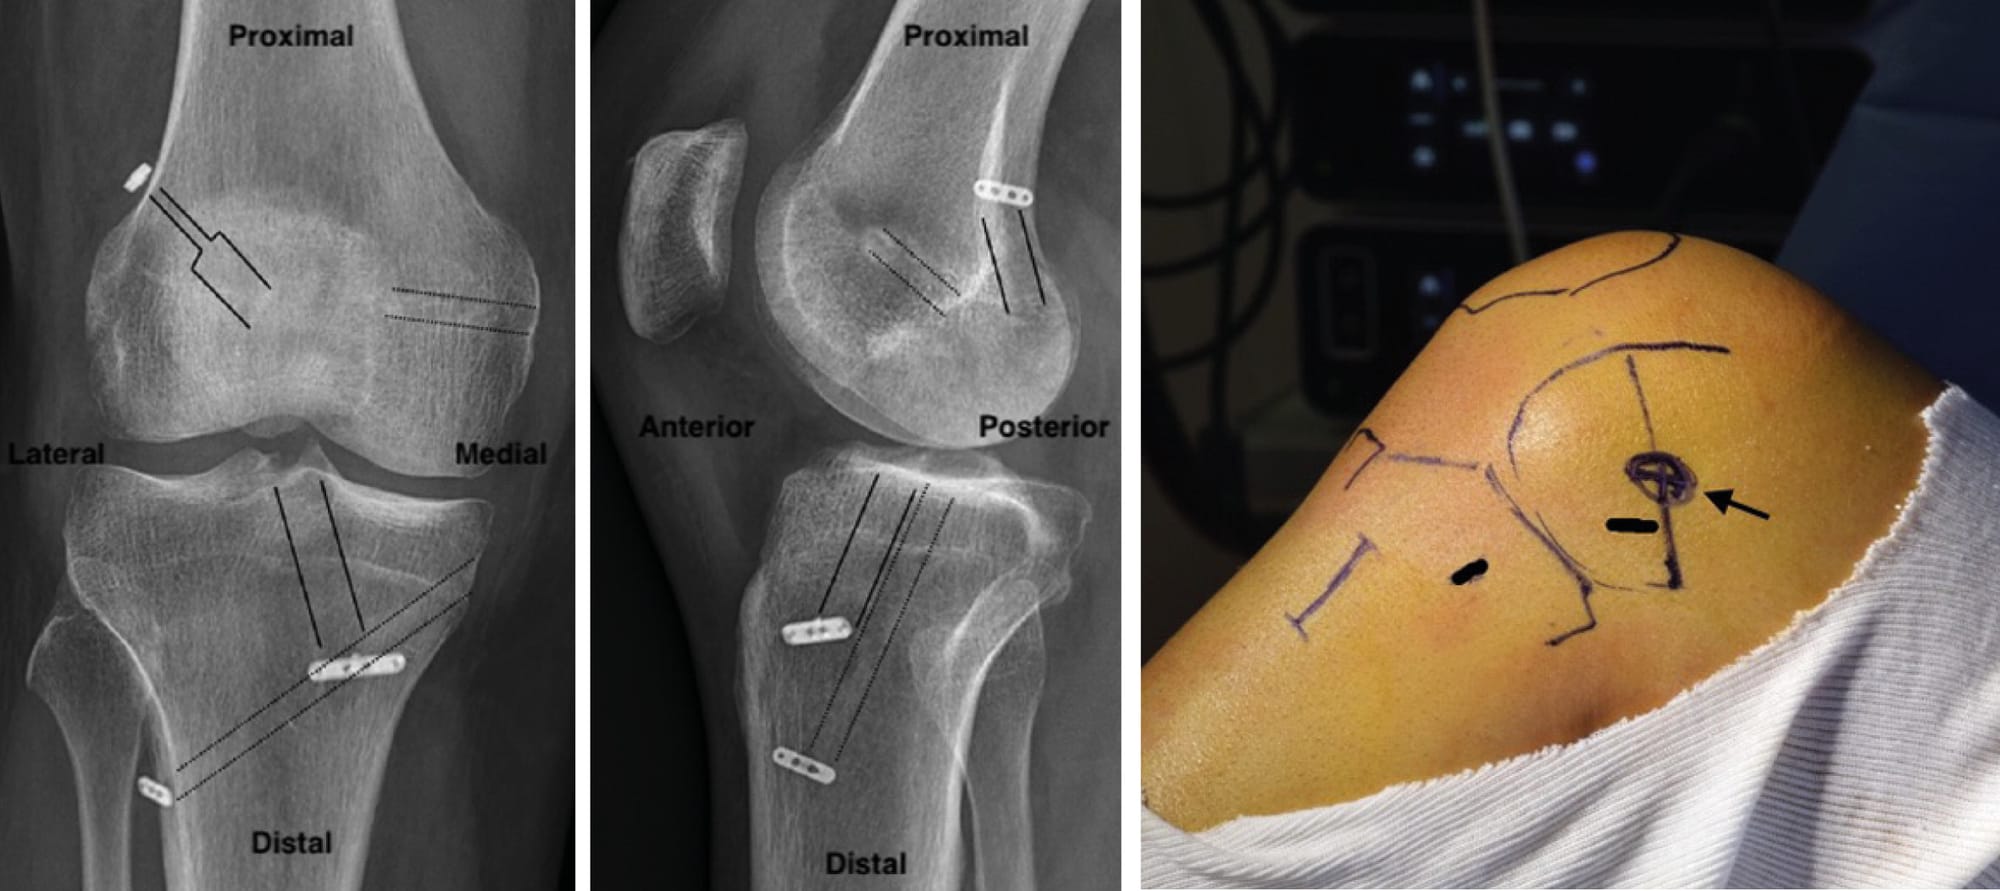

2.2 Biomechanical requirements

In order to comply with the biomechanical requirements, it is important to test the behaviour of the grafts (checking positioning is correct) and to secure the grafts in the right positions (Figure 15).

• Isolated anatomic sMCL reconstruction (Figure 16): This technique can be performed using a percutaneous technique with one incision opposite the medial epicondyle and one opposite the pes anserinus, to create the tibial tunnel for the sMCL and for the ACL.

• Isolated dMCL reconstruction (Figure 17): Mirror Anterolateral Ligament technique, as described by the team at the Clinique du Sport de Bordeaux [10] Daxhelet J, Bouguennec N, Graveleau N. The Mirror Anterolateral Ligament: A Simple Technique to Reconstruct the Deep Medial Collateral Ligament Using the Gracilis Associated With a Four-Strand Semitendinosus for Anterior Cruciate Ligament Reconstruction. Arthrosc Tech. août 2022;11(8):e1419-24. .

• Anatomic reconstruction of the MCL and POL (Figure 18): This technique, first described by Laprade, uses two grafts, the sMCL and POL, which are independent with two tibial tunnels and two femoral tunnels. Now this technique can be performed percutaneously. It is preferable to create an anteroposterior tibial tunnel for the POL to avoid impingement with the ACL tibial tunnel [4] Coobs BR, Wijdicks CA, Armitage BM, Spiridonov SI, Westerhaus BD, Johansen S, et al. An in vitro analysis of an anatomical medial knee reconstruction. Am J Sports Med. févr 2010;38(2):339-47. .